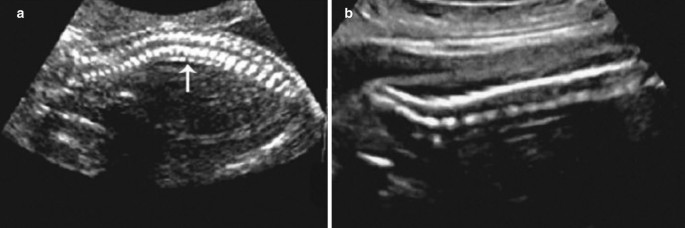

Application Of Diagnostic Ultrasound In The Perinatal Period Springerlink